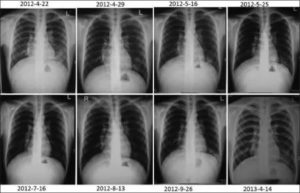

- рентген. Эта процедура назначается в первую очередь при подозрении на пневмонию. Она позволяет определить локализацию воспалительного процесса. На снимке также проявляются патологические изменения в корнях легких;

Грамотный доктор способен определить вялотекущую пневмонию при прослушивании лёгких. Будут слышны звуки от трения плевры и хрипы разного тона. У таких пациентов дыхание обычно жёсткое. Для подтверждения диагноза больной направляется на рентген или МРТ. Эти способы обследования позволяют выявить даже маленькие очаги патологии.

Роль в диагностики этой формы воспаления легких играет не момент начала болезни, а отсутствие положительной динамики при проведении рентгена и наличие повторного обострения в одном и том же месте легкого при правильном лечении и долговременном динамическом наблюдении.